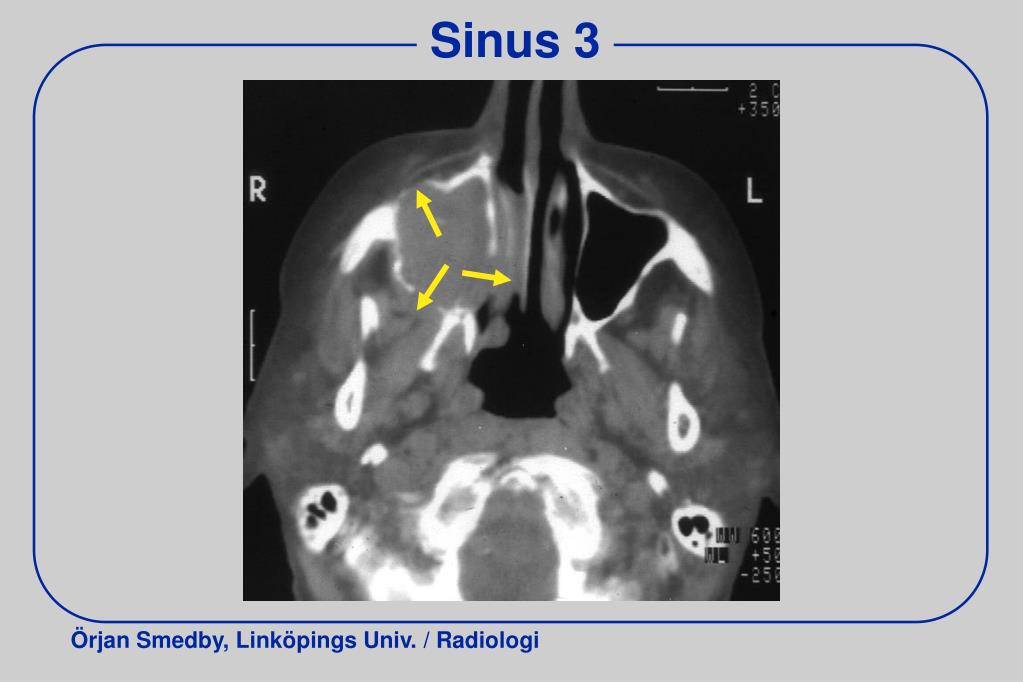

20. Sinus 3

21. Sinus 3 Tumör